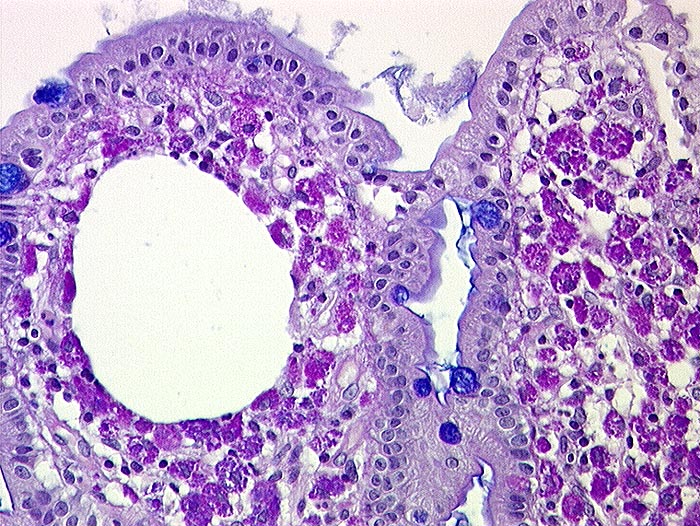

AP/ Morbus Whipple

Morbus Whipple

Dünndarm